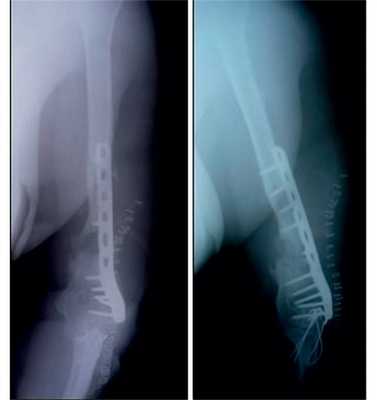

Рис. 12. Рентгенограммы пациентки Н. после операции.

Рис. 13. Рентгенограммы пациентки Н. через 8 мес после операции.